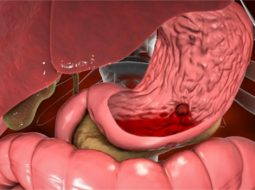

Lão từng gặp không ít bà con, vào đến phòng khám là mặt tái nhợt, môi nhợt nhạt, tay chân lạnh toát… Cứ tưởng thiếu máu thông thường, nhưng bắt mạch, nhìn sắc, hỏi kỹ thì mới vỡ lẽ: đó là hậu quả của xuất huyết dạ dày – căn bệnh âm thầm nhưng nguy hiểm khôn lường nếu không phát hiện và xử lý kịp thời.

- Nôn ra máu, máu đỏ tươi hoặc nâu sẫm như bã cà phê.

- Đi ngoài phân đen, mùi hôi khẳm, dính.

- Hoa mắt, chóng mặt, tụt huyết áp – dấu hiệu mất máu cấp.

Bà con nhớ nhé, chỉ cần có 1 trong các dấu hiệu trên, tuyệt đối không nên coi thường. Bởi mất máu dạ dày nếu kéo dài dễ gây tụt huyết áp, sốc, thậm chí nguy hiểm đến tính mạng.